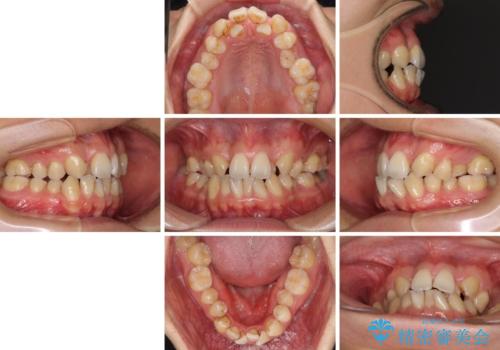

- 前歯の著しいデコボコを気にして来院された患者様です。

上顎の左右側切歯(前から2番目)が裏側に隠れいてる状態で、咬み合わせや清掃性に大きな問題が認められました。

叢生が著しいため、上下左右の小臼歯4本を抜去し、目立たないワイヤー装置にて矯正治療を行うこととしました。

下顎の歯列全体が右側にずれているため、右下のみ第二小臼歯を抜歯し、上顎は補助装置を使用して、極力上下の正中を合う位置にて咬み合わせを改善するようにしました。